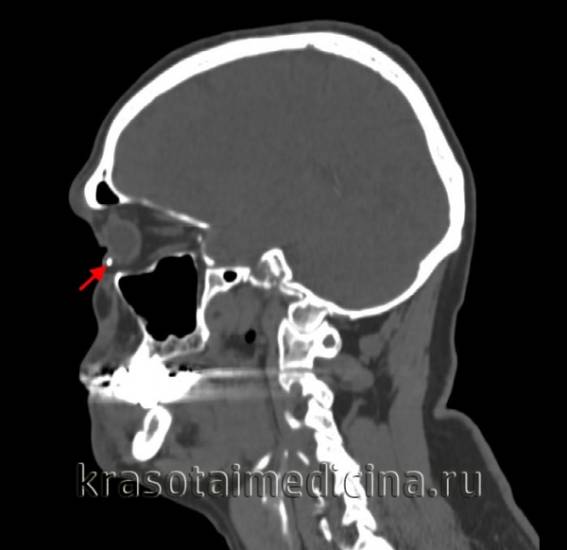

КТ головы. Плотное инородное тело, повреждающее склеру и роговицу.